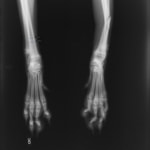

トイプードル 右遠位橈尺骨短斜骨折のALPSによる内固定